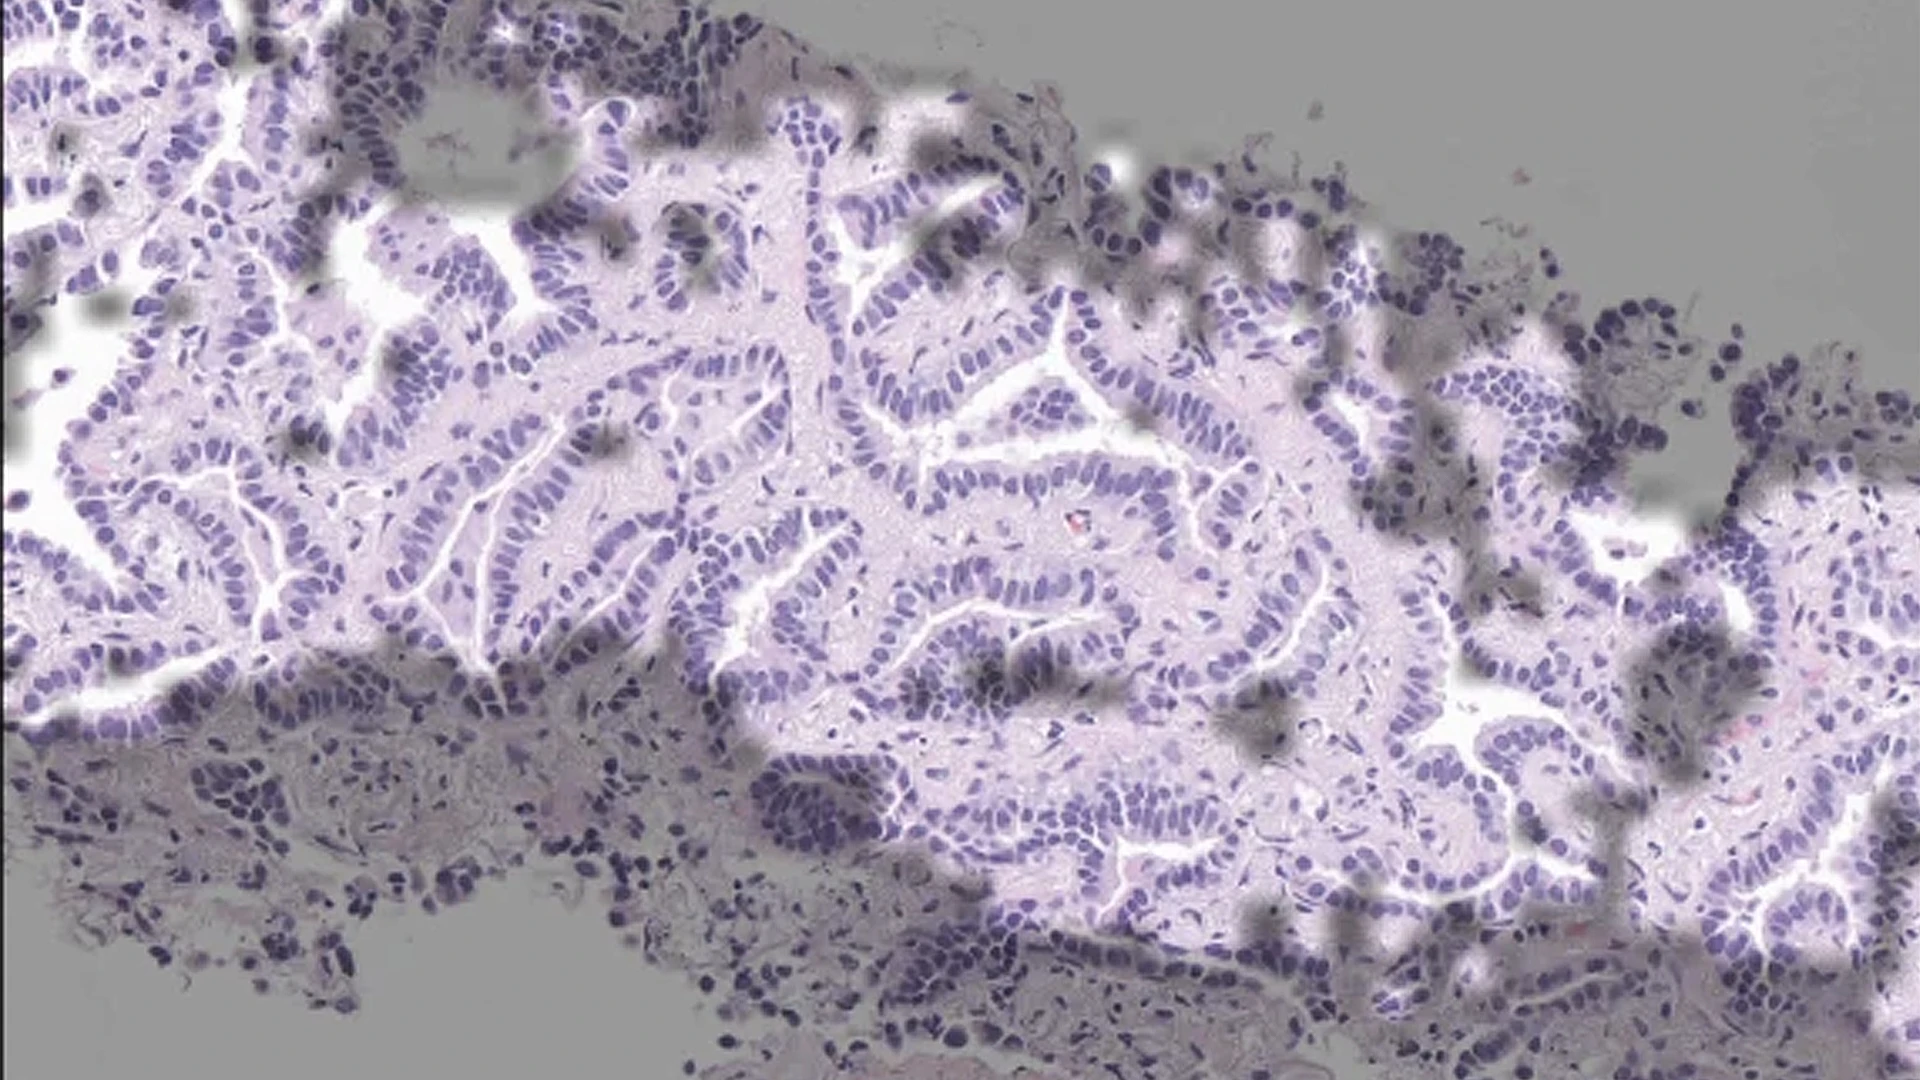

In a real-time “silent trial,” with findings published in Nature Medicine in July 2025, the researchers showed the approach could reliably detect epidermal growth factor receptor (EGFR) mutations in patients with lung adenocarcinoma. Identifying that biomarker is critical: EGFR mutations can drive tumor growth but also render cancers vulnerable to targeted therapies. The AI model could identify likely EGFR mutations faster than standard rapid genetic tests, without exhausting limited biopsy tissue.

To address these limitations, the team leveraged AI, assembling a clinical dataset of more than 8,000 digital pathology slides from patients with lung adenocarcinoma and fine-tuning an open-source machine learning model to identify patterns associated with EGFR mutations. “Our question was: Can we replace rapid tests, at least under certain conditions, with a computational test to speed results and preserve tissue?” Dr. Campanella says.